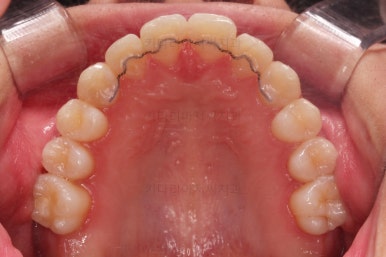

우측 상단에 보이던 어금니도 바로 세운 뒤, 치료를 했습니다.(골드 인레이)

왼쪽 상단으로 보이던 치아도 치료를 했어요.

좌우의 치아가 재료가 차이가 나는데 한 쪽은 튼튼하고 오래 쓸 수 있고 광범위한 부위에 맞는 인레이라는 치료방법 입니다.

왼쪽 치아도 인레이가 추천되는 상황이었지만 경제적인 사정을 고려해서 일단은 건강보험이 적용되는 재료인 GI(지아이)라는 재료로 치료를 했슨비다. 성질이 약한 단점이 있어서 주기적인 체크가 굉장히 중요합니다.

기타 부위들의 디테일을 좀 더 맞춰주고 부산교정 치료를 종료합니다.

전후사진을 비교해 볼게요.

약간의 주걱턱, 돌출입은 고칠 의사가 없어서 그대로 유지하였고 주걱턱 패턴으로 인한 부정교합 부분을 개선했으며 무엇보다 중요한 것은 쓰러져서 많이 썩어있던 치아를 자칫 치료 못할 뻔 했는데 교정치료와 병행하여 훌륭하게 치료를 하여 살려 썼다는 점입니다.